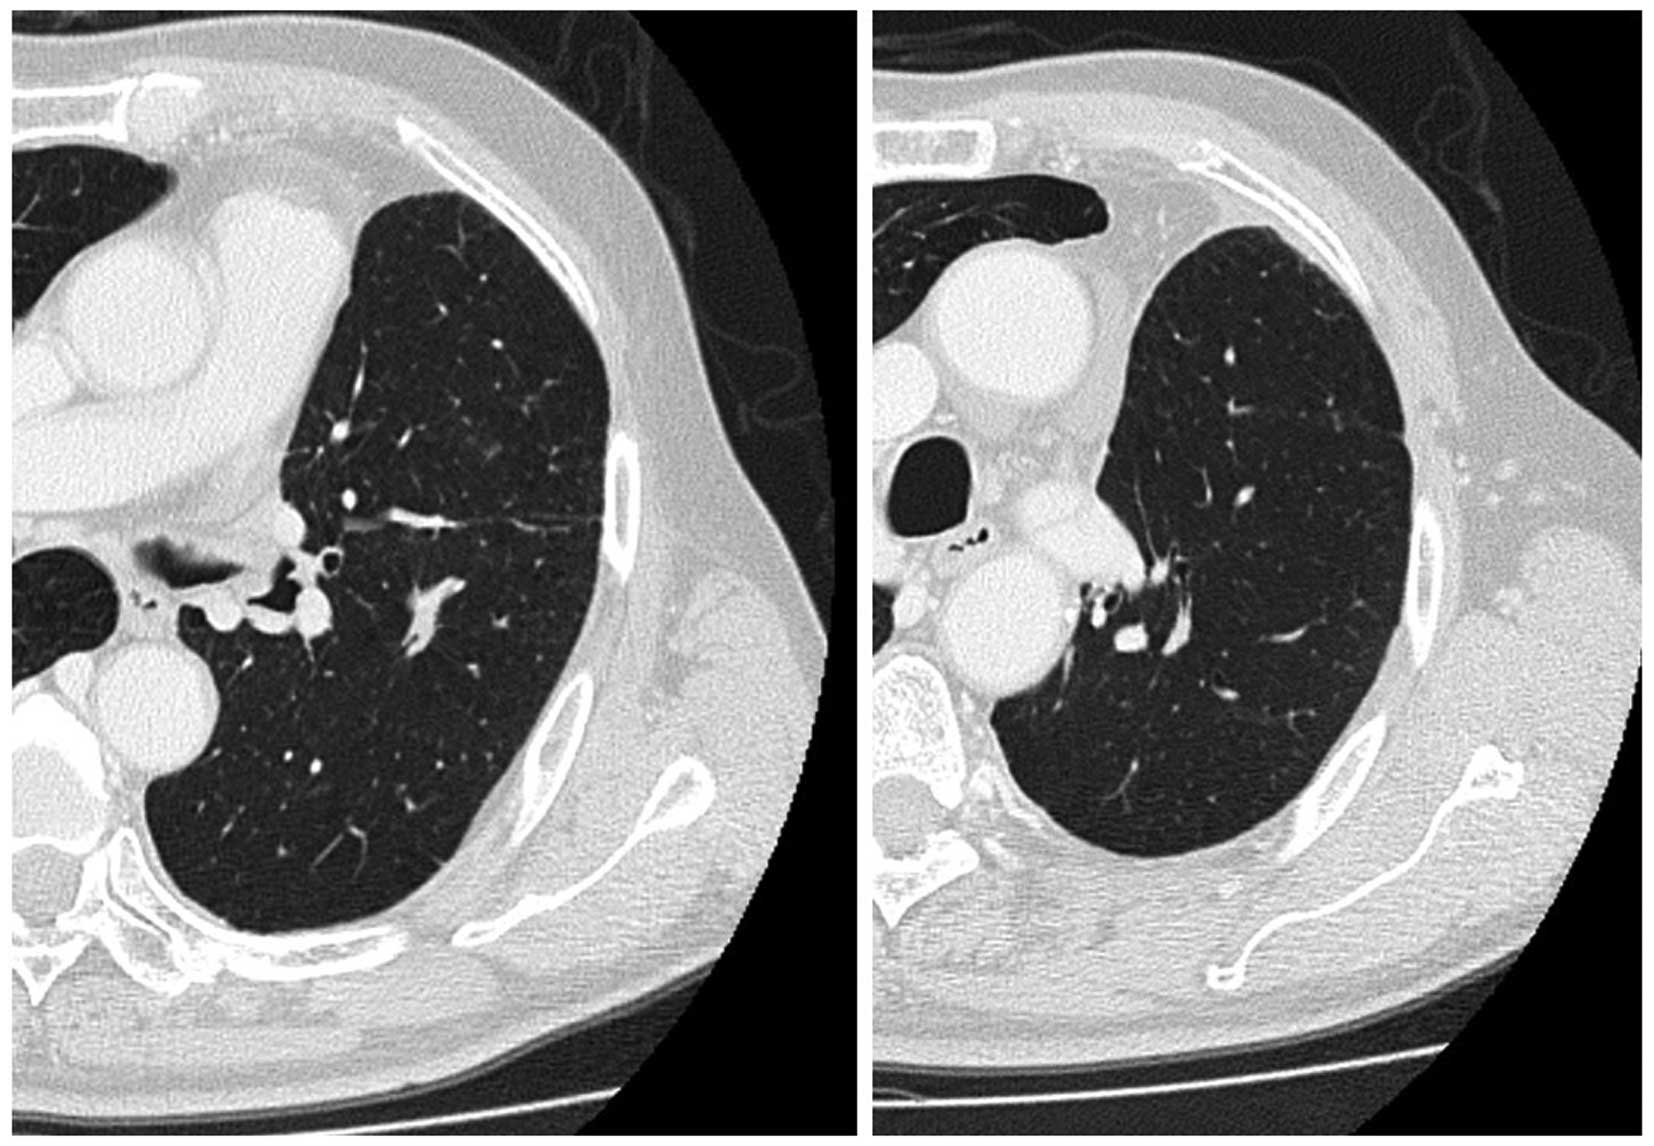

A 68-year-old man was admitted to the hospital with a productive cough. A chest radiograph revealed a tumor 5 cm in diameter in the right lung. Bioptic specimens, which were obtained transbronchially, were diagnosed as NSCLC. As the patient did not present with hilar/mediastinal lymph node enlargement or distant metastasis, he underwent right upper pulmonary lobectomy. On postoperative pathological examination, the tumor was diagnosed as pleomorphic carcinoma of the lung (Fig. 1). The examination for epidermal growth factor receptor mutations was negative. As there was microscopic involvement of the ipsilateral mediastinal lymph nodes, 4 courses of postoperative chemotherapy containing cisplatin and vinorelbine were administered. Four months after the end of the treatment (10 months after the diagnosis), the disease recurred as two pulmonary nodules ≤1 cm in diameter in the left lung, detected on follow-up chest computed tomography (CT) scan (Fig. 2). The work-up for systemic metastasis was negative. Two courses of chemotherapy, consisting of carboplatin [area under the curve (AUC) = 5, day 1, q28 days), pemetrexed (500 mg/m2, day 1, q28 days) and bevacizumab (15 mg/kg, day 1, q28 days) was performed, and the post-treatment evaluation CT scan revealed shrinkage of the two pulmonary lesions (Fig. 3). Thereafter, the patient received an additional two courses of chemotherapy. A follow-up CT scan revealed further shrinkage of the pulmonary tumors. The patient received 20 courses of maintenance chemotherapy consisting of pemetrexed (500 mg/m2, day 1, q28 days) and bevacizumab (15 mg/kg, day 1, q28 days) without any severe adverse events. No recurrence was found and the patient remained well for 30 months after the initiation of the chemotherapy for recurrence; however, the patient succumbed to brain infarction.